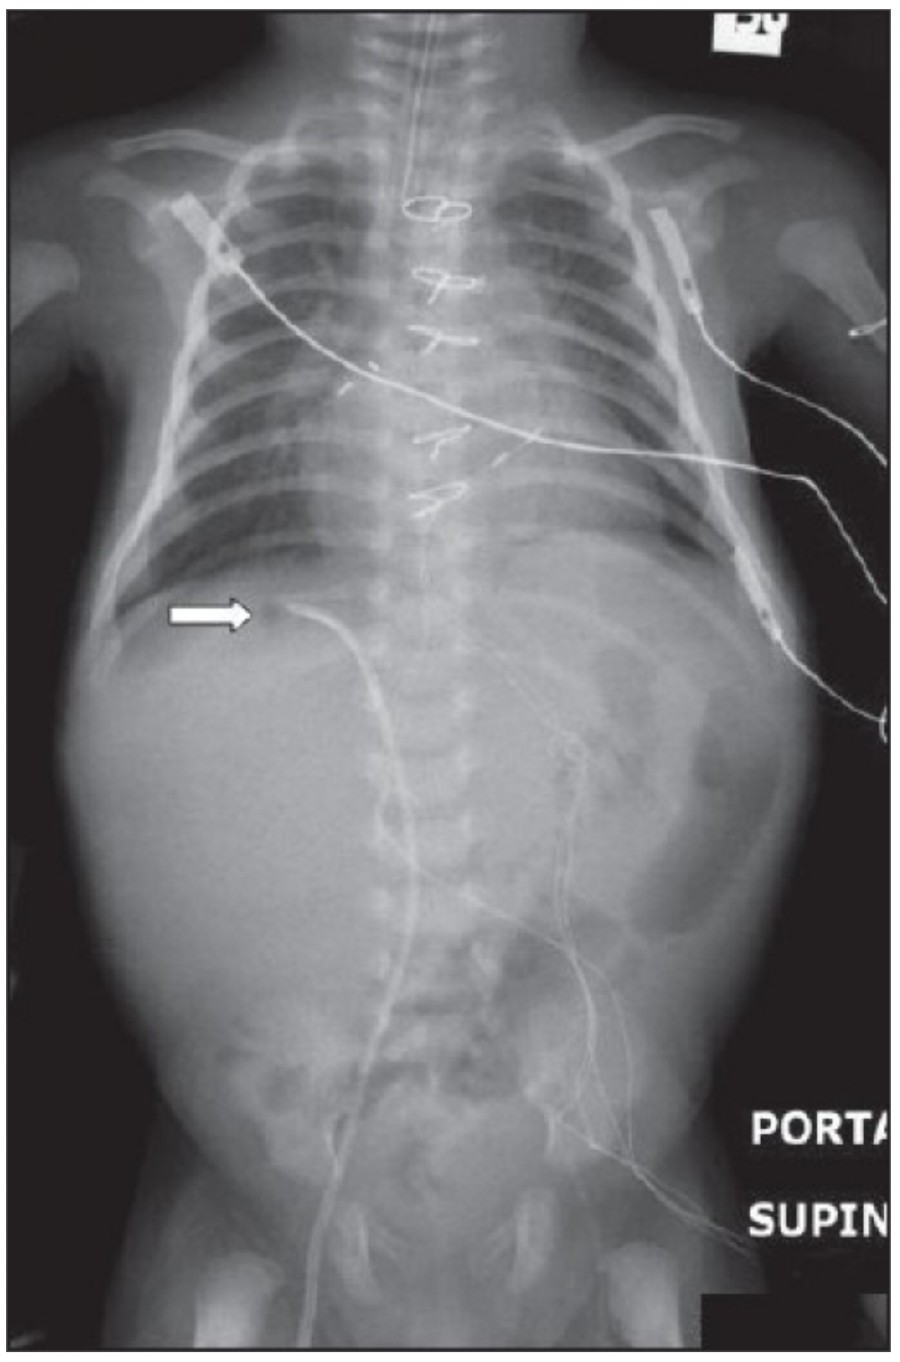

방사선 소견상 Pleural effusion은 환자 흉부의 dependent area에 고인다. Erect position에서 확인하기가 쉬운데, 폐의 base에 고임으로써 costophrenic angle blunting을 보이고 lower lobe vessel들의 흐리게 한다. Supine position에서는 확인이 더 어려운데, pleural fluid는 posterior basilar space에 고여서 폐 base 쪽으로 intensity가 증가하는 homogenous density를 보인다. 정상적인 bronchoalveolar marking은 이와 같은 veil-like density 안에서 확인 가능하다. Fluid 양이 늘어나면서 diaphragm의 윤곽이 흐릿해지고 costophrenic angle도 없어지는데, 이 costophrenic angle blunting이 없더라도 pleural space에 1L 정도의 pleural fluid가 있을 수 있다는 것을 기억해야 한다. 그 양이 더욱 늘어날 수록 fluid는 lung의 apex에서 pleural cap으로 나타날 수 있으며, 이는 supine position에서도 확인 가능하다. Pleural fluid는 lung의 medial side에 고일 수도 있으며 이는 mediastinum의 확장으로 보일 수도 있다.

적은 양의 pleural fluid는 꼼꼼히 확인하더라도 supine radiograph에서 놓칠 수 있는데, 만약 chest X ray에서 보이지 않지만 임상적으로 의심이 되는 경우에는 lateral decubitus film으로 확인해 볼 수 있다. Fluid는 dependent position에 고이므로 환자를 의심되는 방향으로 옆으로 눕혀야 한다. Lateral decubitus film은 적은 양의 pleural fluiid는 물론이고 loculated effusion과 free effusion을 확진하는 데도 도움이 된다. 특히 loculated effusion은 한 개 이상의 drain이 필요할 수 있으므로 pleural drainage를 고려할 때 특히 중요한 검사이다. 중환자에서 흔하게 나타나는 subplumonic effusion은 lung base에 존재하는 pleural effusion을 말하는데, chest X ray 상에서 raised hemidiaphragm with flattening and lateral displacement of the dome 형태로 나타나며, lateral decubitus film이 도움이 된다.